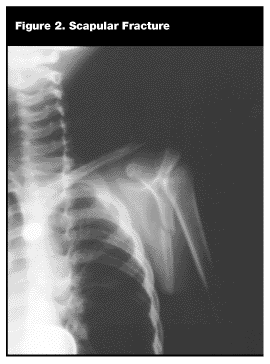

Scapula. Fractures of the scapula are rare in children and usually occur as the result of direct high-energy trauma or a crush injury and frequently are associated with other, more serious injuries. On examination, pain usually is noted over the scapula, and the child will be reluctant or unable to move the upper arm. Plain AP radiographs usually will reveal the fracture. (See Figure 2.) Tangential or oblique views are sometimes necessary, however, to see the fracture. Most fractures are not displaced. Treatment for the isolated scapular fracture is a sling and swathe for 3-4 weeks.4,5